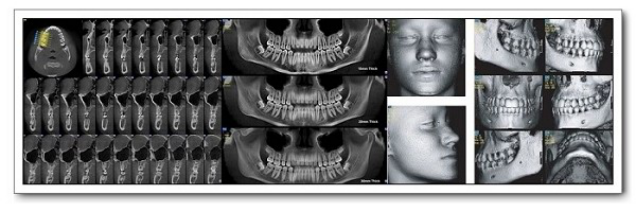

新疆医科大学附属口腔医院影像科是拥有多台先进数字化医学影像设备和较高专业技术水平的口腔影像专业化科室。新疆医科大学口腔医院影像科现有医护人员7名。具有硕士以上学历人员占比50%科室现有原装进口的德国口腔signora锥形束CT机一台,卡瓦Aero-X三合一一台,芬兰instrumentarium数字化曲面体层摄影机1台,卡瓦RVG一台,美国柯达数字rvg一台。主要开展医疗项目有对口腔颌面部囊肿、肿瘤、外伤、炎症、颞下颌关节、涎腺、牙体...查看详情 >